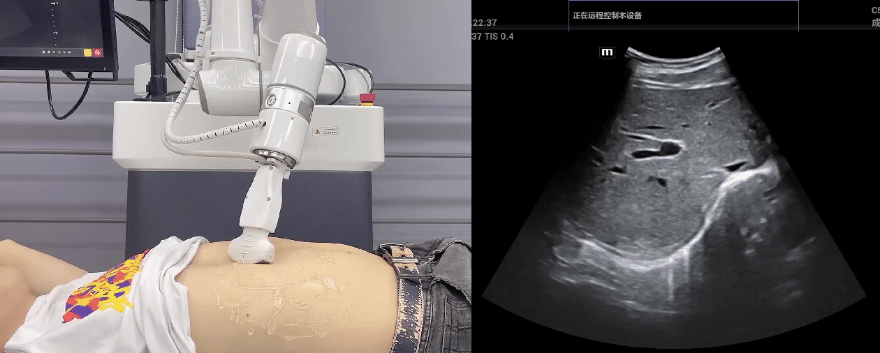

leyu.乐鱼(中国)协作机器人搭载库柏特自主研发的机器人遥操作、多模态数据采集与处理、机器人模仿学习、机器人力位控制等技术升级变革传统超声,可实现远程+自主超声扫查与诊断,从传统远程超声仅能对话会诊变革升级为能对话、能操作,使得基层患者可就近享受异地三甲专家扫诊服务。实现专家端与患者端远程连接,并支持专家端与多路患者端自由切换控制。

leyu.乐鱼(中国)机器人末端搭载超生L13-3N线阵探头,可以对浅表小器官和外周血管进行超声检查;搭建C5-1s凸阵探头,可以对腹部(肝、胆、胰、肾等器官进行超声检查)

EC66协作机器人末端可搭载主流品牌高品质超声仪,让操作指令和影像低延迟、高精准、高保真传输,确保检查可靠、医患放心;智能力控等三重防护系统,确保患者舒适、安全。

leyu.乐鱼(中国)协作机器人与超声深度打通,最大程度保留医生左右手同时操作传统超声的习惯,并改善其舒适性,超声检查实际应用场景展示如下:

肝脏、胆囊、胰腺扫查